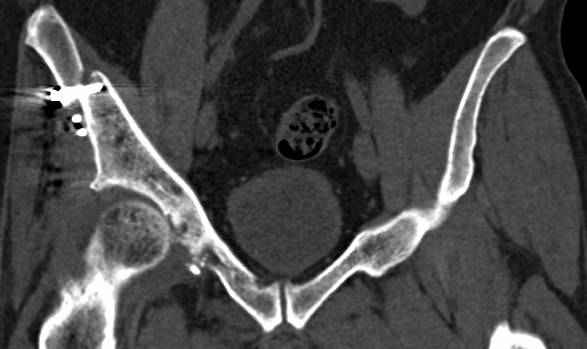

высылаю дополнительно сканы.

итак, второй вариант: высокий двухколонный с вовлечением КПС... Ни одно из основных повреждений не репонировано, кроме задней стенки. Скорее всего попытка реконструкции вертлуги сейчас будет очень травматичной и не очень эфективной, т.е. вероятный риск более значим, чем ожидаемая польза... Лучше подождать, и потом сразу эндопротез

подождать сколько, чего? такая дыра в задней колонне не закроется никогда.

потом эндопротез какой? в такой ситуации приходит на ум Burch-Schneider cage, в 35 лет, дальше что делать?